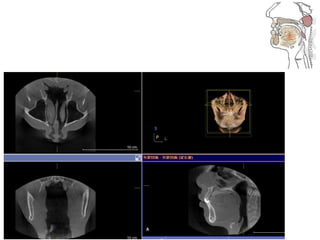

• 46.

• 62.

• 63.